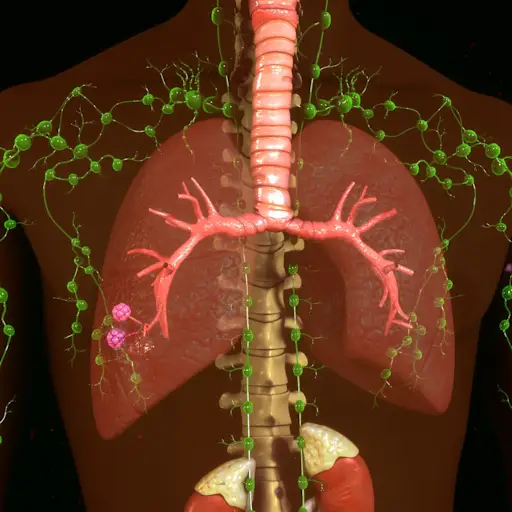

理论6:是你的淋巴系统

这是一个新兴的理论。根据克利夫兰诊所的说法,淋巴系统是免疫系统的一部分,如果工作正常,可以保护身体免受致病问题的影响,保持体液,并清除废物。当它不正常时,问题就会发生。根据最近的一项研究,该理论认为淋巴结与深层的、浸润性的子宫内膜肠病变有关生殖科学,这也表明内膜细胞从循环系统和淋巴系统移动到身体的不同部位(甚至肺、眼睛和大脑),在那里植入形成新的内膜病变。